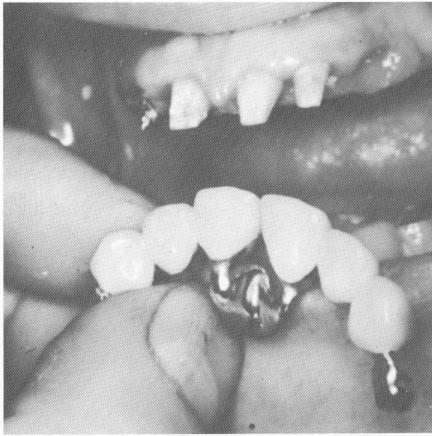

The castings were fitted in the mouth and a wax

Fig. 15-100. The anterior restoration—both quadrants joined by a palatal plate—was fitted in the mouth. The diastema was still present.